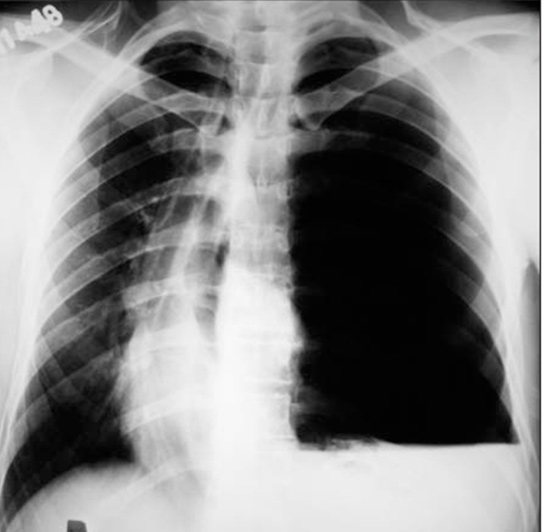

Tansiyon pnömotoraksın teşhisi, klinik muayene ve görüntüleme yöntemleriyle konur. Doktor, hastanın semptomlarını değerlendirir ve aşağıdaki yöntemlerle tanıyı kesinleştirir:

• Göğüs röntgeni: Hava birikimini tespit etmek için kullanılır.